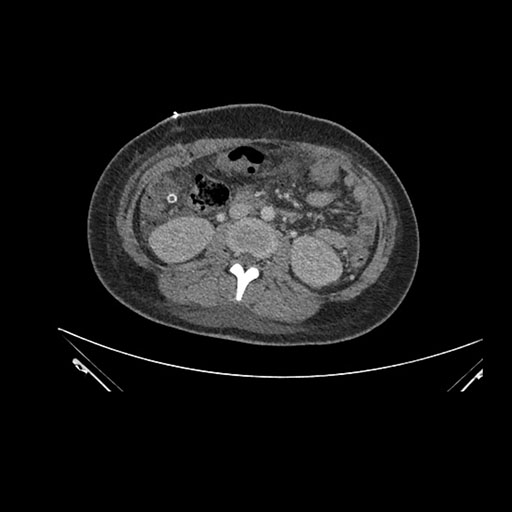

Imaging Analysis

Look through the patient's CT scan to identify any areas of concern for the necessary procedure.

Axial Venous

Based on initial findings, which issue(s) would you be most concerned about?